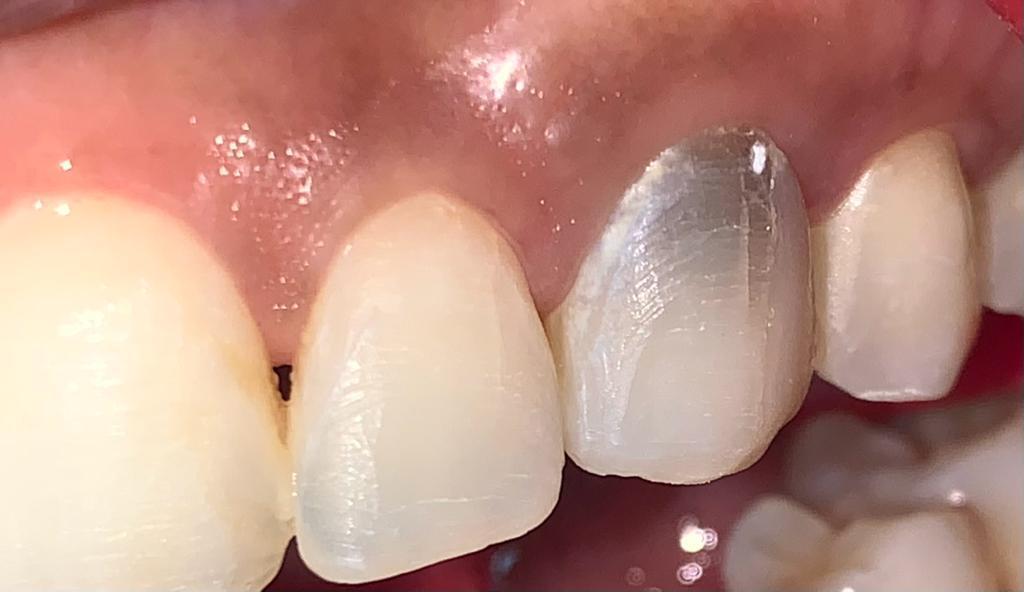

Antes de tratamiento - diente manchado post-endodoncia

Antes

Blanqueamiento Interno

Paciente con diente manchado post-endodoncia que afectaba significativamente la estética de su sonrisa y su confianza.

Después de tratamiento - corrección de diente manchado

Después

Blanqueamiento Interno - Resultado

Resultado final del Blanqueamiento Interno